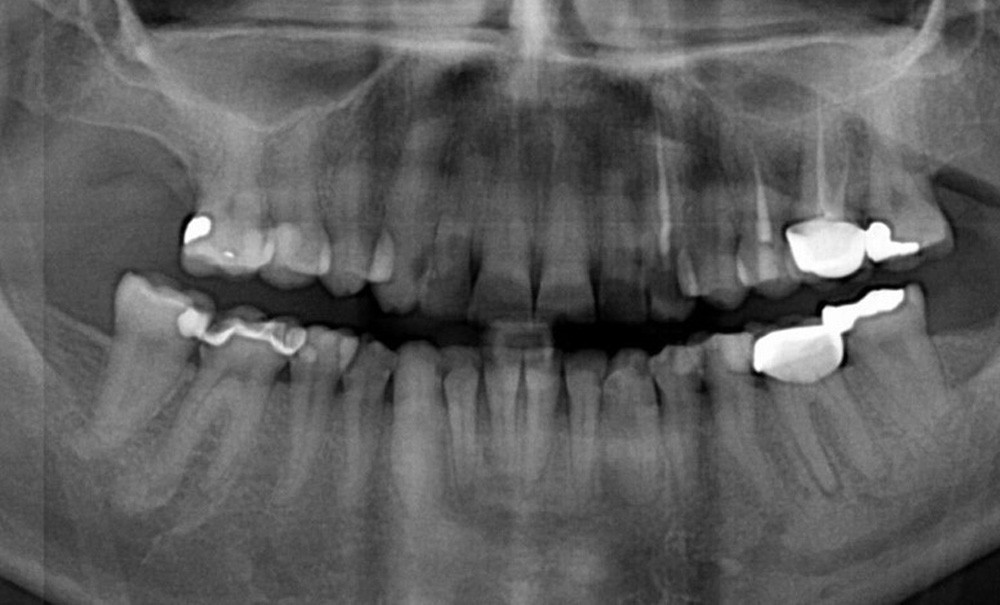

Les troubles des conduites alimentaires, en particulier l’anorexie mentale et la boulimie sont des troubles graves, évoluant sur une longue durée. Les complications physiques et psychologiques sont sévères avec un retentissement individuel, familial et social majeur, car trop souvent les soins ne sont pas suffisamment précoces. Au niveau bucco-dentaire, une prévalence accrue de récessions gingivales et de lésions d’usure dentaire, majoritairement érosives, est retrouvée. Le challenge thérapeutique est grand pour le chirurgien-dentiste, car les patients consultent souvent quand les lésions sont avancées et dans un contexte médical où les facteurs de risque ne sont pas contrôlables… Les recommandations de la Haute Autorité de Santé pour la prise en charge par le chirurgien-dentiste sont aujourd’hui d’une aide précieuse pour conduire, étape par étape, un traitement parodontal et restaurateur sûr et efficace.

La première étude clinique sur les complications bucco-dentaires des TCA a été publiée il y a plus de 40 ans et a rapporté une prévalence élevée d’usure érosive, de caries et de perturbations salivaires dans une cohorte de 39 femmes âgées de 14 à 42 ans souffrant d’anorexie mentale [2]. Les revues systématiques publiées depuis concluent à un risque augmenté de lésions d’usure érosives et de lésions carieuses liées aux perturbations alimentaires et aux vomissements [3, 4]. Les complications parodontales ont été étudiées plus récemment. Une prévalence accrue de gingivite liée à la plaque et de récessions gingivales a été observée [5]. Toutefois, très peu d’études cliniques se sont intéressées au versant thérapeutique, qu’il soit restaurateur ou parodontal, dans cette population à besoins spécifiques. Le praticien est ainsi souvent dérouté devant des situations cliniques complexes lorsque les patients consultent tardivement et dans un contexte où les facteurs de risque sont peu contrôlables. Cet article a pour objectifs de rappeler les recommandations de prise en charge pour le chirurgien-dentiste des personnes avec un TCA développées par la Haute Autorité de Santé (HAS) (https://www.has-sante.fr/upload/docs/application/pdf/2019-09/fs_boulimie_prise_en_charge_dentaire_v2.pdf)…